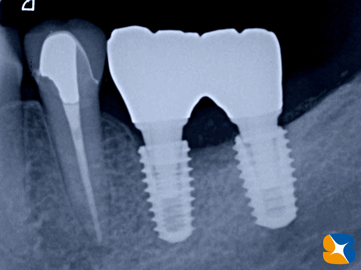

精密なレントゲン撮影を行うと、やはりインプラントを支える周囲の骨が、溶けて無くなっていました。

林楊春先生 推奨 メガジェン直径4㎜と4.5㎜、長さ8.5㎜のインプラントを移植に使用しました。

レントゲンでチェック。大きく失われていた下顎の骨も順調に再生しています。